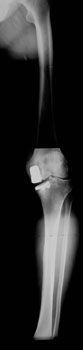

Mise au point Stratégie diagnostique dans les pentades et les luxations du genou , Dominique Saragaglia Service de Chirurgie Orthopédique et de Traumatologie du Sport C.H.U. de Grenoble - Hôpital Sud, Grenoble, France , C. Chaussard Service de Chirurgie Orthopédique et de Traumatologie du Sport CHU de Grenoble, Hôpital Sud 38130 Echirolles N°143 - Avril 2005 ● 23 min de lecture